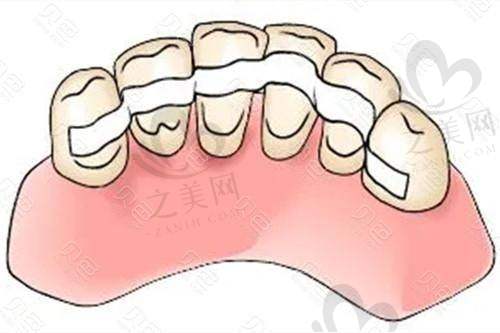

作为以种植牙为特色的口腔医院,重庆种博士口腔不仅掌握传统种植牙技术,还引进和吸收了即时种植、ALL - ON - 4、ALL - ON - 6等高难度种植技术。医院可根据虚拟手术规划数据,使用CAD/CAM技术或3D打印机制作个性化的手术导板,借助导板在更小切口中精细定位并植入种植体,减少组织损伤并缩短修复时间。同时,医院擅长采用微创技术和理念,减少患者痛苦和修复时间,提高缺牙患者治疗的安心性和舒适度。

除了种植牙,医院还开展牙齿矫正、牙齿美容、牙周病治疗等多元化服务。它是时代天使、隐适美授权机构,矫正方案采用精良设计;拔牙、根管治疗可全程打“睡眠麻醉”,让患者在舒适的状态下完成治疗。